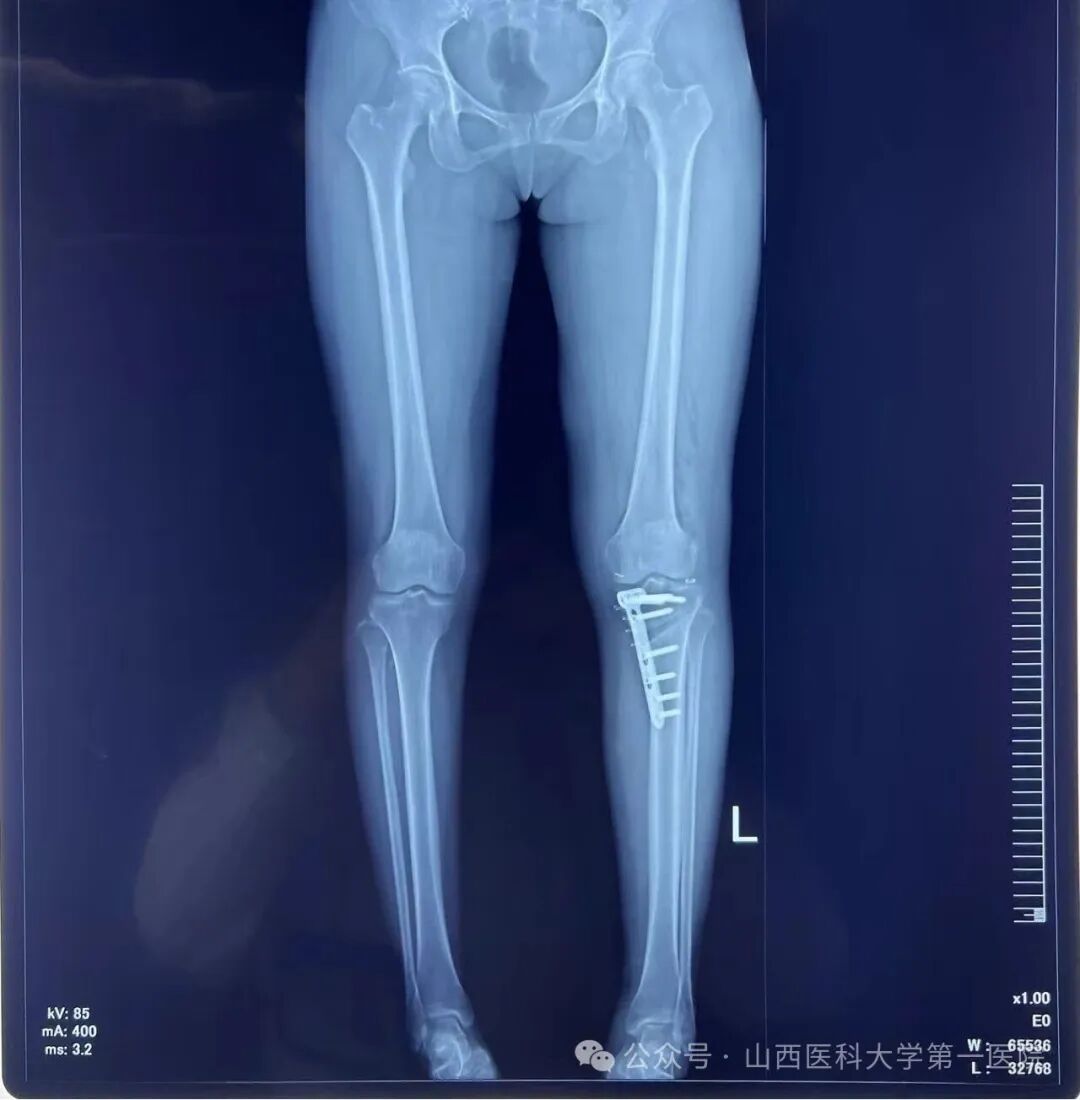

术后左下肢力线明显矫正